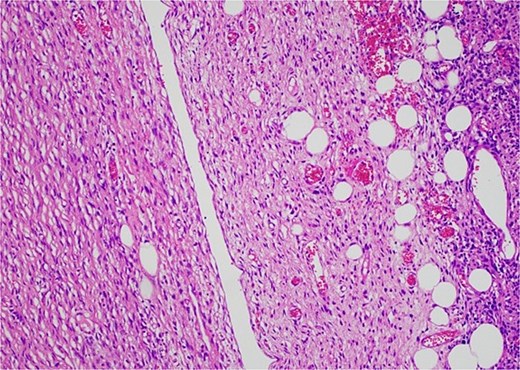

Histology revealed a multilobulated spindle cell lesion, with low- and high-grade areas, with an abrupt transition between these areas. There was an adjacent focus of adipose tissue with rare cytologic atypia suggestive of possible WDL, which indicated that the tumor mass may represent DDL. However, there was a single focus of lipoblasts identified, bringing up the differential of pleomorphic liposarcoma. Therefore, in situ hybridisation was performed and showed MDM2 amplification, which confirmed the diagnosis of DDL, with likely homologous lipoblastic morphology. The tumour was excised with clear margins (Figs 3–8).

Low-grade component with spindle cells with tapered nuclei and indistinct cytoplasm that merges into a delicate collagenous stroma.

Low-grade component with abrupt transition to high-grade component (asterisk).